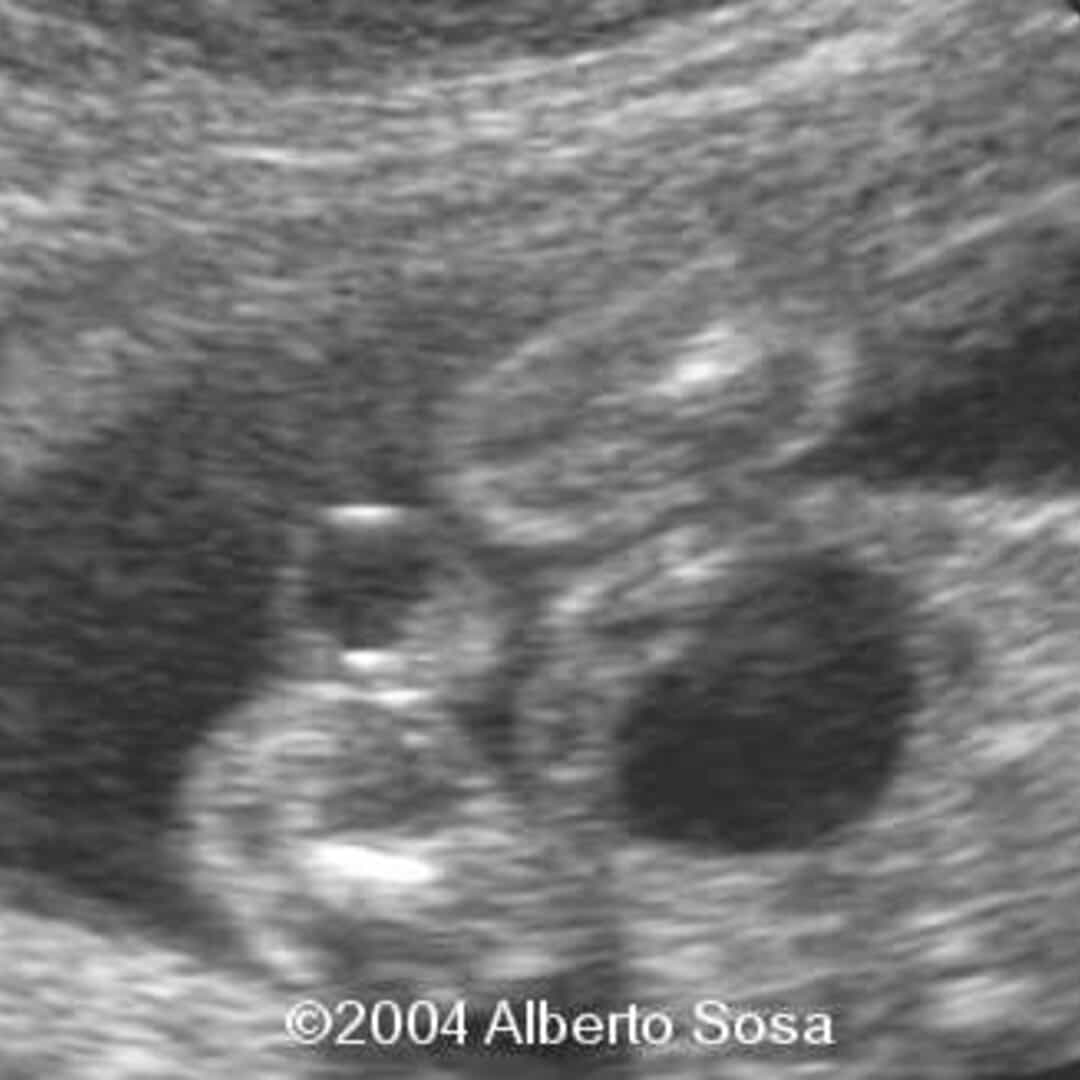

Ultrasound images of Horseshoe kidneys Radiology Imaging Horseshoe Kidney In Fetus horseshoe kidney, also called renal fusion, is a condition that starts before a child is born. As a baby develops in the. horseshoe kidney occurs during fetal development, as the kidneys move into their normal position in the flank area (area. Usually, two individual kidneys form in. horseshoe kidney is a condition that develops when a fetus. Horseshoe Kidney In Fetus.

Ultrasound image of the horseshoe kidney Download Scientific Diagram Horseshoe Kidney In Fetus horseshoe kidney, also called renal fusion, is a condition that starts before a child is born. Horseshoe kidney is found in 30% of cases of turner syndrome and in 20% of trisomy 18. horseshoe kidney occurs in about 1 in 500 children. horseshoe kidney is when the 2 kidneys join (fuse) together at the bottom. A fetal. Horseshoe Kidney In Fetus.

Horseshoe Kidney Ultrasound, Sonography, Radiology Horseshoe Kidney In Fetus It occurs during fetal development as the kidneys move into their normal position from the pelvis. Usually, two individual kidneys form in. horseshoe kidney is when the 2 kidneys join (fuse) together at the bottom. They form a u shape like a horseshoe. horseshoe kidney, also called renal fusion, is a condition that starts before a child is. Horseshoe Kidney In Fetus.